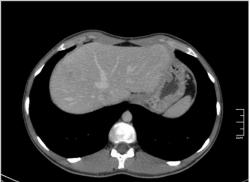

КТ печени. Наблюдения для размышления.

Уважаемые коллеги, особенно врачи КТ. Надеюсь что данная публикация окажется полезной для многих из Вас. Ниже представлены сканы печени; предлагаю Вам ознакомится с ними и высказать свое мнение. Пациент мужчина средних лет, специфичных жалоб не предъявляет.

Если Вы не против, я немного придержу продолжение данного наблюдения. Основная задача данной публикации не сам диагноз, а показать современные аспекты и особенности метода КТ, а также важность глубины и объёма знаний врачей радиологов которые занимаются КТ диагностикой.

Уважаемый v1tal! Огромная Вам благодарность; Вы назвали ключевое слово: фаза! Высказанная Вами мысль, это моя основная цель данной публикации. Постараюсь позже более детально объяснить почему. Представленные сканы выше, были выполнены на стандартной портальное фазе. А сейчас, я покажу сканы данного пациента выполненные на артериальной фазе :

Да Ola la, Вы абсолютно правы; это Фокальная Нодулярная Гиперплазия печени (FNH Focal Nodular Hyperplasia). Одна из немногих гиперваскулярных опухолей печени. Наверное некоторые коллеги спросят, и зачем было изначально публиковать портальную фазу, на которой «не видно» (хотя опухоль видна, пусть и не напрямую, и Nela это доказала); и только потом показывать сканы на артериальной фазе, на которой всё «красиво и показательно». Постараюсь объяснить.

За эти два года, в течении которых я познакомился с радиологическим русскоговорящим интернетом, я пришёл к определённым выводам. К сожалению, при наличии уже довольно неплохого парка современной аппаратуры в клиниках России и СНГ (у меня лично аппаратура намного скромнее по возможностям чем например у Nela или v1tal), ощущается огромный пробел в знаниях очень многих врачей, которые работают на этих аппаратах. И как следствие, врачи классические рентгенологи, отправляя пациентов на до-обследование в эти клиники, получая при этом неудовлетворительный результат проведённых исследований, начинают полагать (и имеют на это право), что зачем все эти «КТ и МРТ», если мы по своим стандартным рентгенологическим методикам получаем тот же результат (если иногда и не лучше-живой пример тому публикация vital с дивертикулом пищевода, где врач КТ написал диафрагмальную грыжу). И когда я читаю такие посты, мне становится очень обидно, хотя повторюсь, я уже пониманию причины такого мышления. Тем более что мало кто знает, что КТ и МРТ это не «статические методики», при которых взял пациента, положил на стол, дал контраст (как, куда, на какой скорости-мало кого волнует), сделал одну спираль/фазу, и до свиданья, «подавайте» следующего. Современные протоколы КТ и МРТ выработаны ПОД КАЖДЫЙ КОНКРЕТНЫЙ ДИАГНОЗ, иными словами, если мы подозреваем заболевание кишечника, и снимем пациента по протоколу разработанному для диагностики патологии печени или поджелудочной, то мы можем пропустить «всё на свете» в кишечнике, и при этом ничего не найти в печени или панкреас.